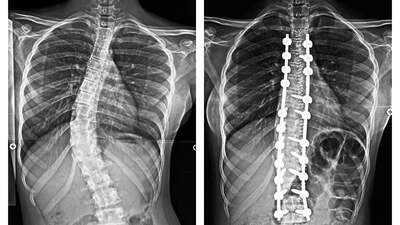

Severe scoliosis, a condition where the spine curves abnormally like a bow, affects posture, breathing, and daily activities. At Wockhardt Hospitals, Mumbai Central, her spine curved across 12 vertebrae – nearly her entire backbone. Mild cases can be managed with observation or braces, but surgery was the only solution for her.

Under the supervision of Dr. Mazda Turel, Consultant Brain and Spine Surgeon at Wockhardt Hospitals, the surgery involved a midline incision, carefully placed screws and rods, and gradual correction of the twisted vertebrae. The meticulous procedure restored alignment, levelled her shoulders, and corrected her waist balance.